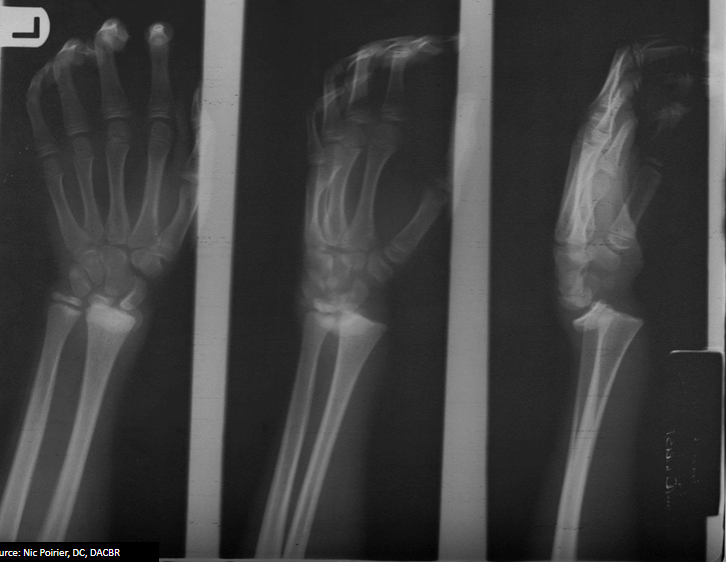

5

Q

What is the diagnosis for the fracture of the radius and the causative mechanism?